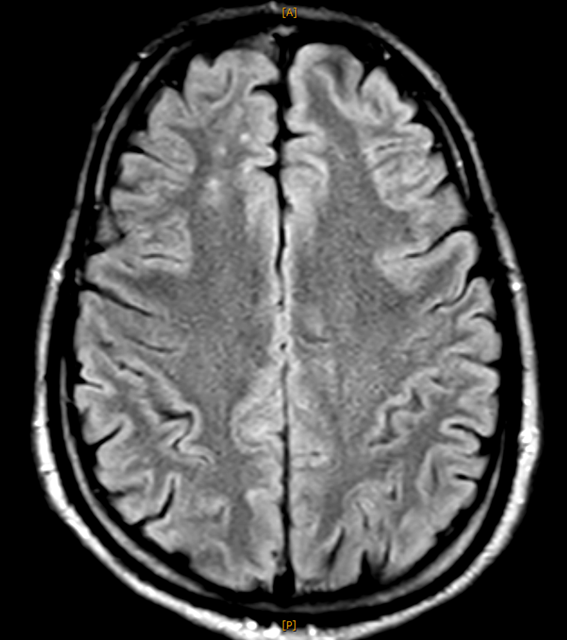

以下、今回撮られたMRI画像です。いずれも 右前頭葉に脳挫傷性の変化 が認められます。

これらは びまん性軸索損傷 の所見です。

脳挫傷やびまん性軸索損傷を示す画像所見が認められることが必要になります。

本件では、上記のとおり、はっきりとした画像上の異常所見があり、これにより脳挫傷、びまん性軸索損傷と診断されました。